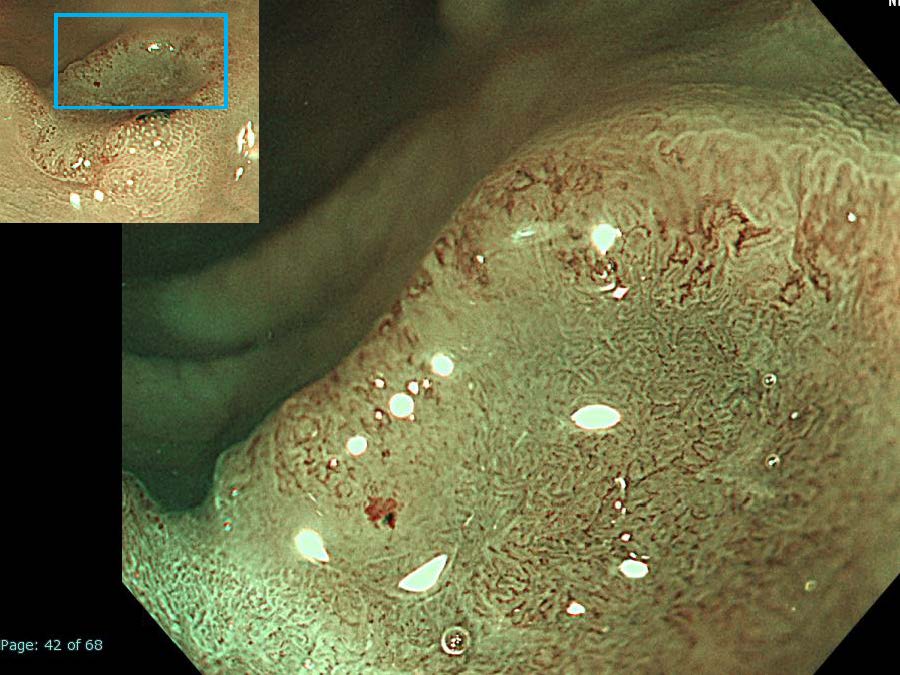

消化管Mapping~大腸~ 2021.10.27

消化管Mapping~大腸~

内視鏡検査・治療

消化管Mapping